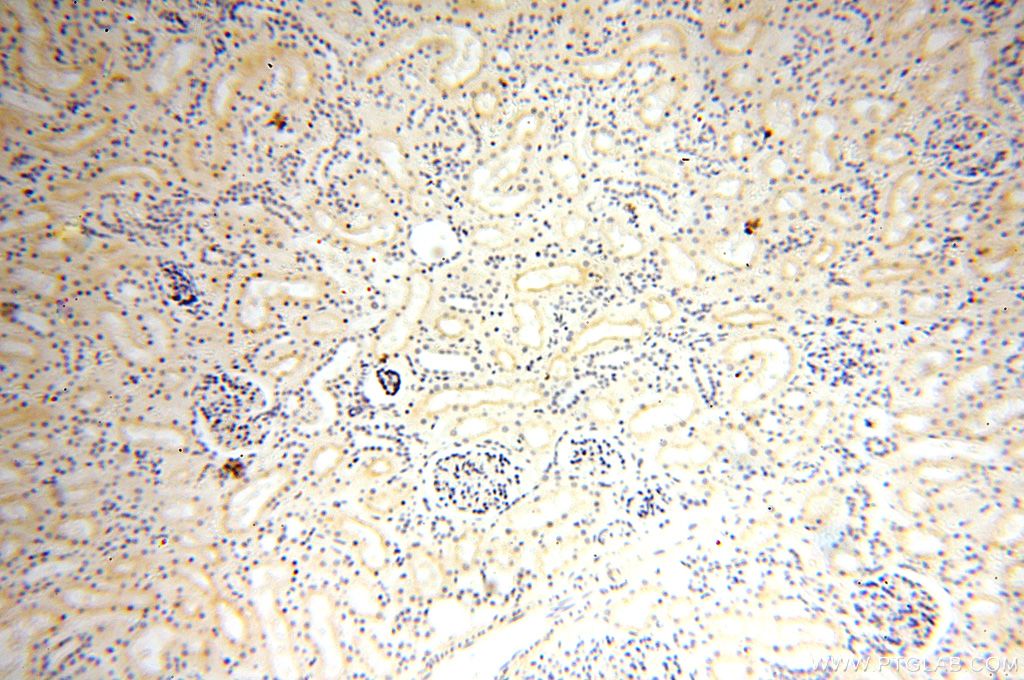

| Positive IHC detected in | human kidney tissue Note: suggested antigen retrieval with TE buffer pH 9.0; (*) Alternatively, antigen retrieval may be performed with citrate buffer pH 6.0 |

| Immunohistochemistry (IHC) | IHC : 1:20-1:200 |